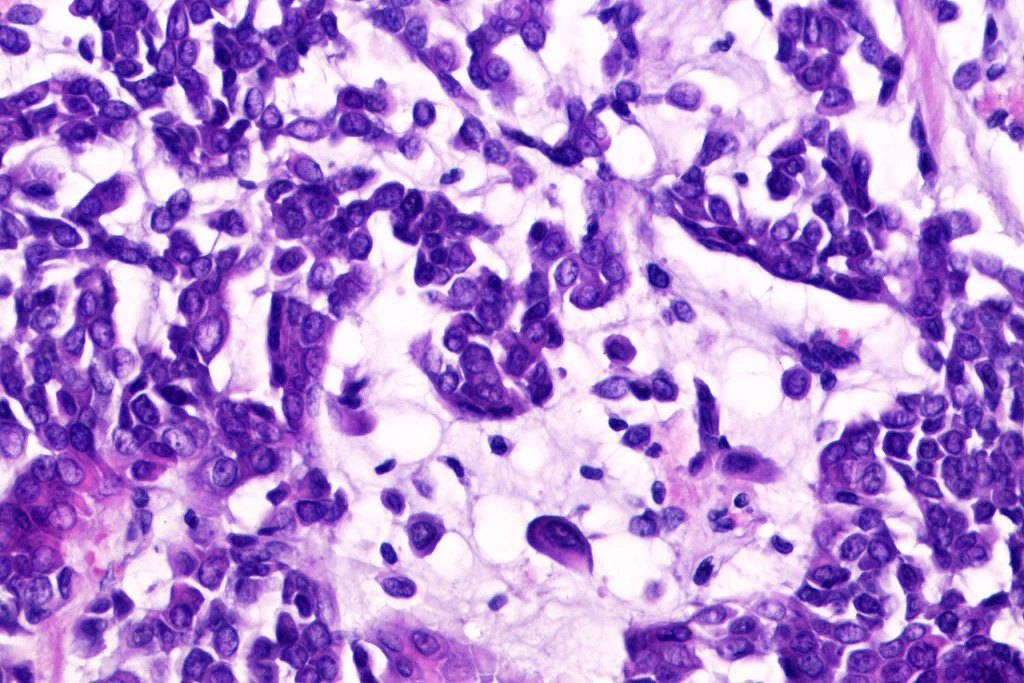

Histological features

•Infiltrative growth pattern

•Nuclear pleomorphism, prominent nucleoli

•Marked mitotic activity

•Abnormal mitoses

•Lymphovascular invasion

•Carcinosarcoma

•IHC is similar the same as for the benign tumor